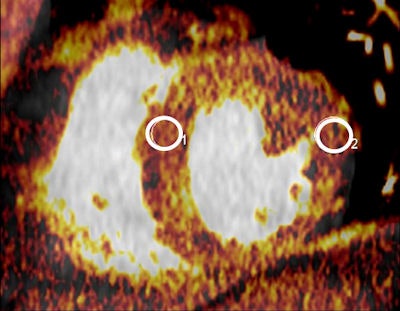

The researchers equipped an anthropomorphic phantom with tubular inserts containing known iodine concentrations from 20 mL in the cardiac chamber, and fat rings to simulate different patient sizes. Dedicated software was used to measure iodine concentrations at DECT and the results were compared to true concentrations. Linear regression models to identify predictors of measurement accuracy.

The results showed excellent correlation between measured and true iodine concentrations in 72 datasets across both CT systems and multiple protocols ( r = 0.994 - 0.997, p < 0.0001). The mean measurement errors between real and measured CT values were 3.0 ± 7.0 % for first-generation scanners and -2.9 ± 3.8 % for second-generation dual-source CT.

The group also reported a significant (p = 0.002) interaction between true iodine concentration and phantom size, and measurement accuracy decreased with increasing phantom size. The mean error was -0.8 ± 3.9% without the fat ring simulating larger patients, 2.0 ± 4.9 % when a five-cm fat ring was used, and 8.3% when a 10-cm fat ring was used. And overall accuracy of iodine measurements was better for 100 kVp than for 80 kVp, especially at lower iodine concentrations, the study team wrote.